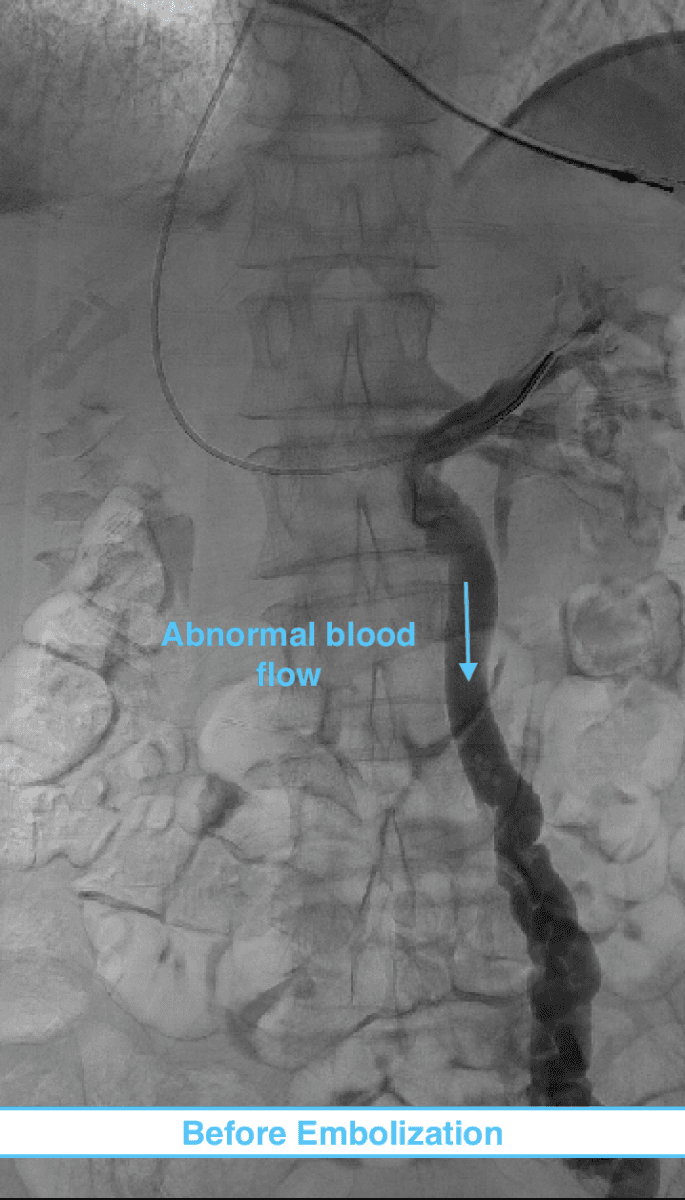

During this procedure, our image-guided specialist will numb the skin and insert a catheter (a tiny tube) into a vein in the neck or groin. The placement is done with precision using ultrasound guidance minimizing pain.

Using x-ray guidance a smaller catheter is then guided into the abnormal ovarian or pelvic veins. The abnormal vein is then treated by placing tiny coils and a specialized fluid causing the vein to seal down. This then restores normal blood flow in the body and improves related symptoms.